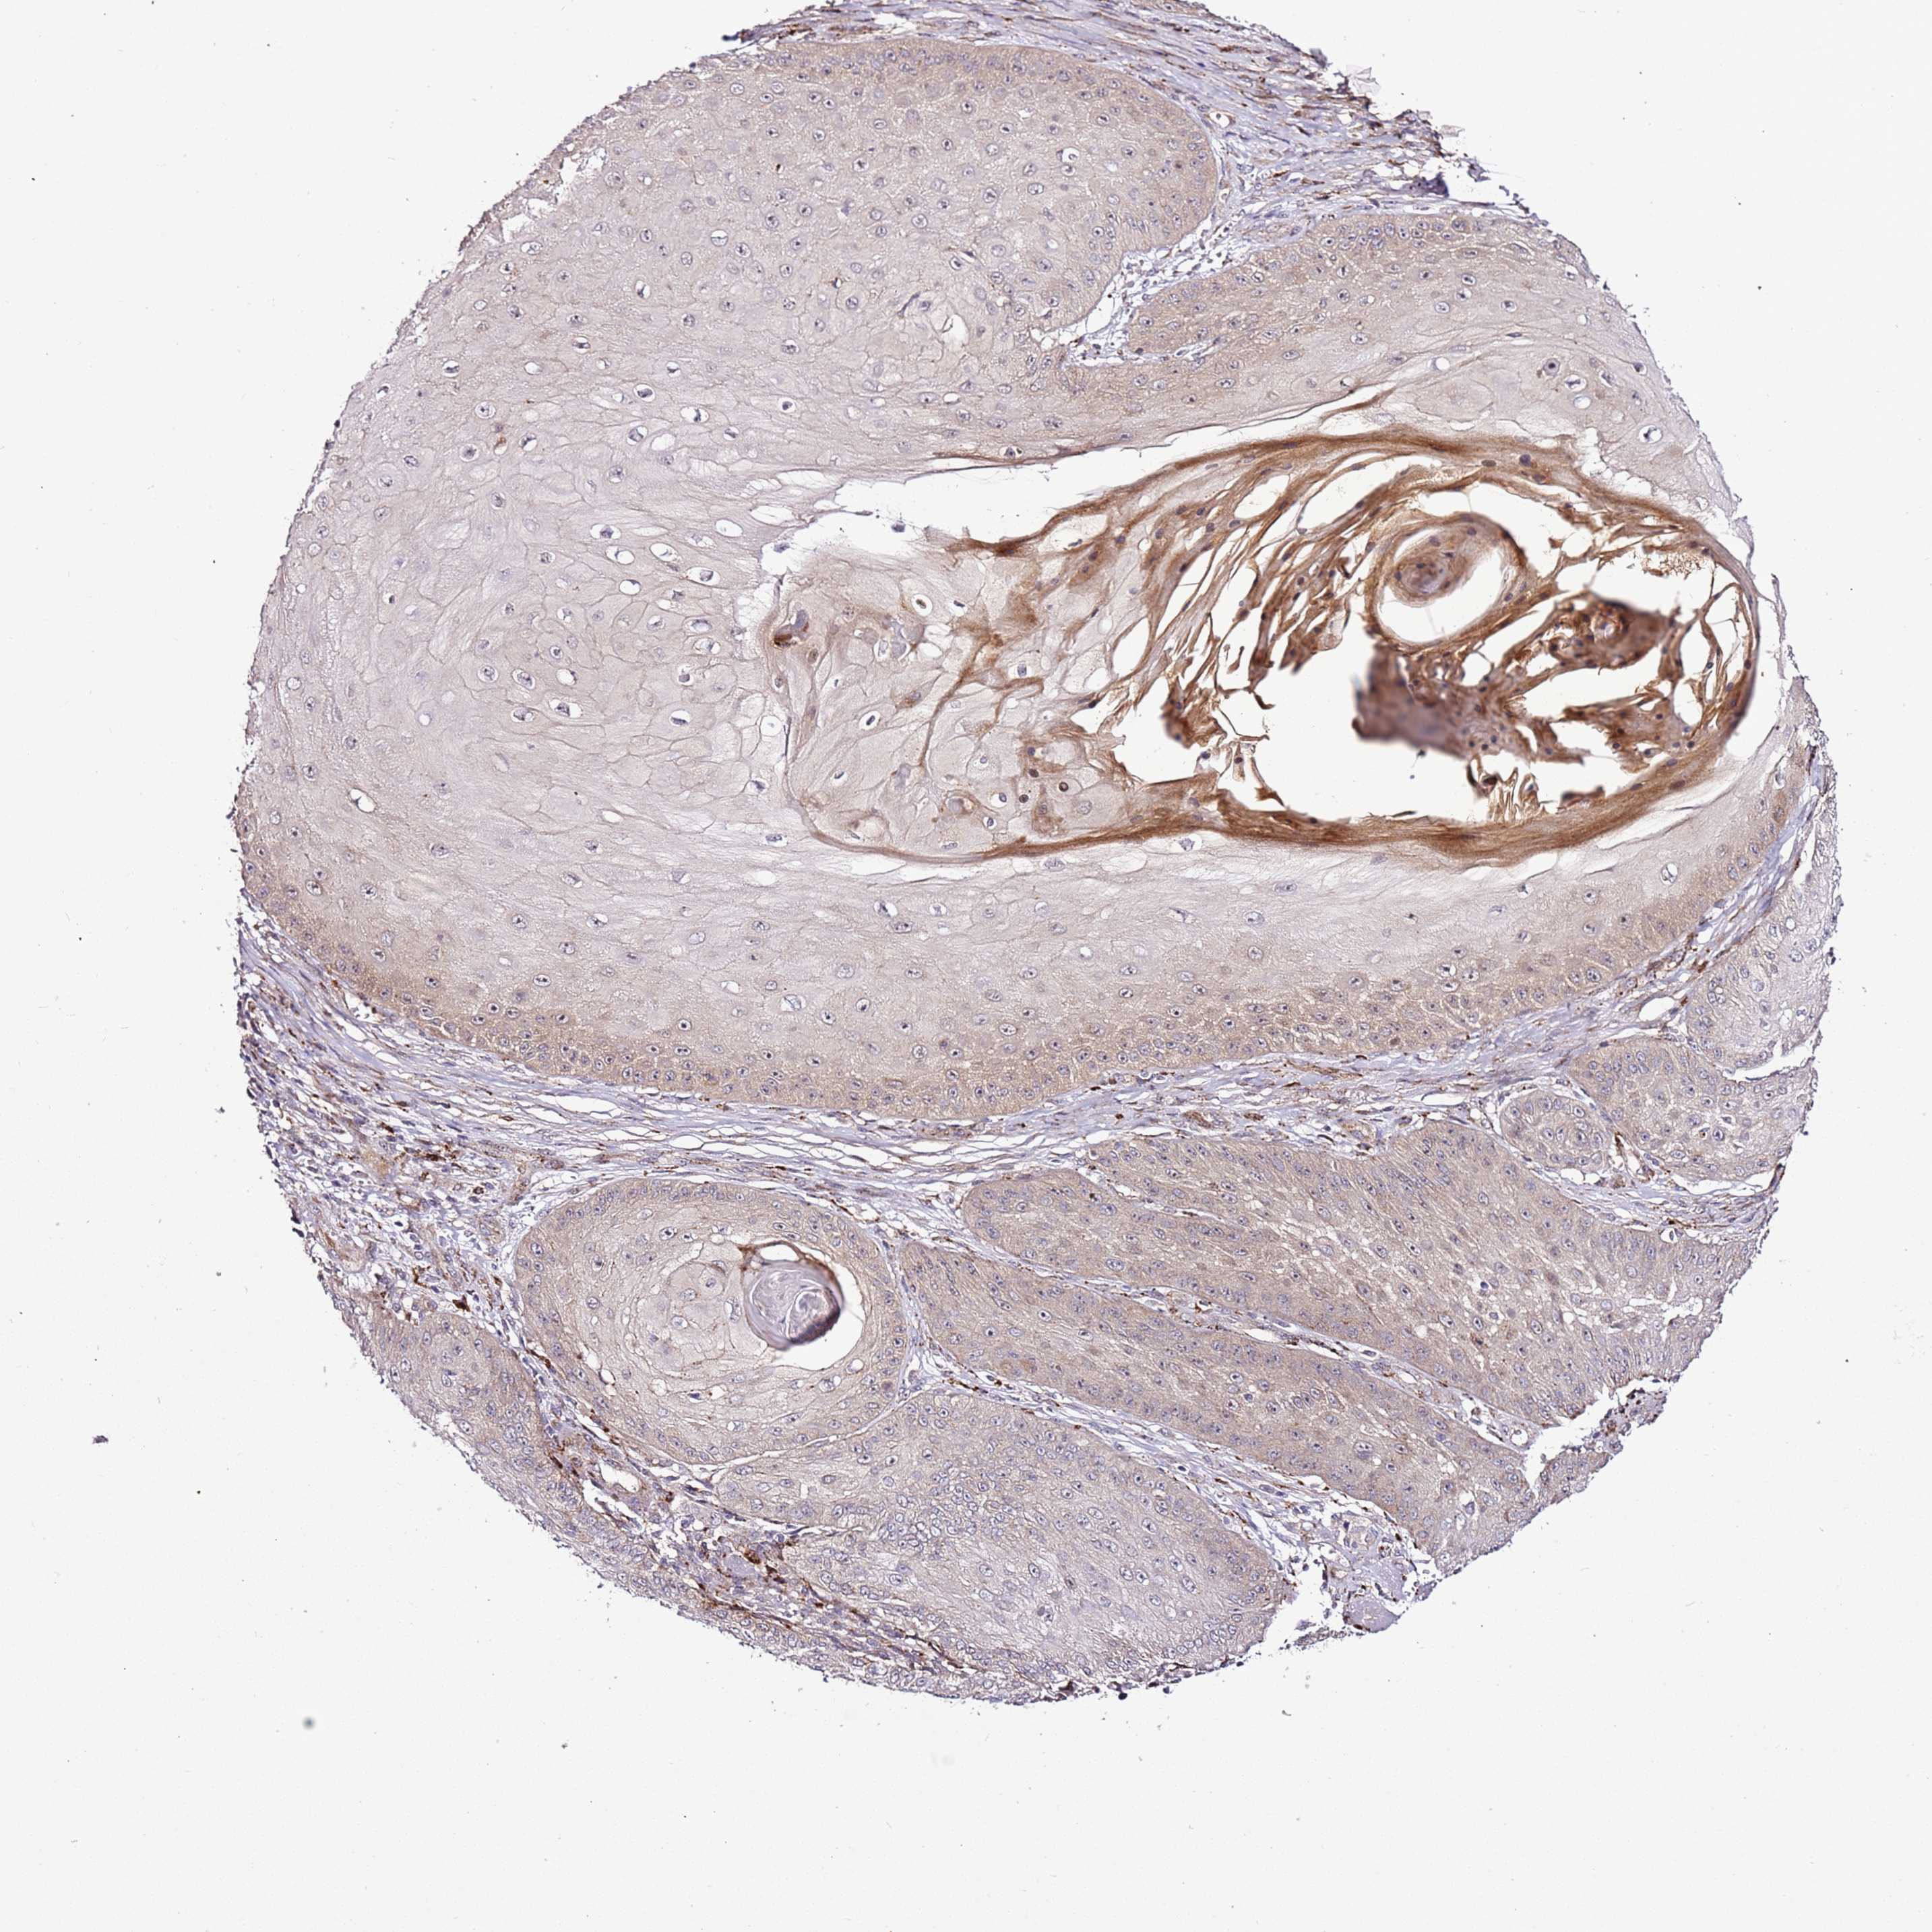

Basal cell and squamous cell cancer

SKIN CANCER - Protein expressioni

A mouse-over function shows sample information and annotation data. Click on an image to view it in a full screen mode. Samples can be filtered based on level of antibody staining by selecting one or several of the following categories: high, medium, low and not detected. The assay and annotation is described here.

Each image is clickable and will lead to virtual microscopy that enables deeper exploration of all samples and also displays staining intensity scores, fraction scores and subcellular localization as well as patient and tissue information for each sample.

Antibody HPA047497

Staining

High

Medium

Low

Not detected

Intensity

Strong

Moderate

Weak

Negative

Quantity

>75%

75%-25%

<25%

None

Location

Nuclear

Cytoplasmic/membranous

Cytoplasmic/membranous,nuclear

Squamous cell carcinoma, NOS